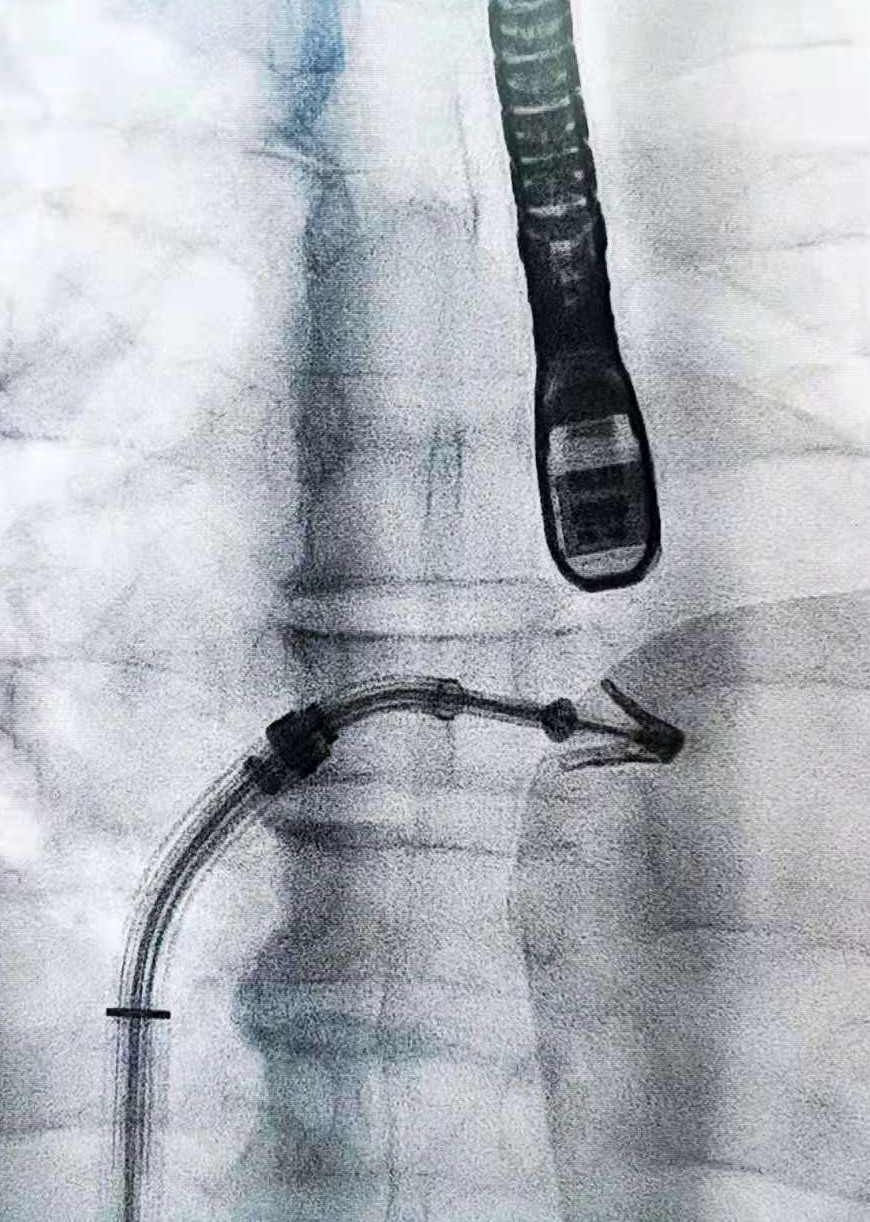

王焱教授(右一)率团队实施我国首例二尖瓣机械瓣术后的Venus A Plus瓣膜植入。

心脏瓣膜团队不满足于此,他们紧随国际医学前沿,运用先进治疗方案,挑战高难度病例。今年,微创瓣膜手术进一步得到完善:2月,团队运用我国首个可回收瓣膜系统——Venus A Plus瓣膜为已多次进行心脏手术的老人更换瓣膜,完成了我国首例二尖瓣机械瓣术后的Venus A Plus瓣膜植入;3月,采用经皮穿刺微创介入方案为生命垂危的七旬老人进行联合双瓣膜置换术,在同一台手术中更换了主动脉瓣膜和二尖瓣膜,全国尚属首例;4月,在省内率先完成经导管二尖瓣钳夹术,成为中国大陆第五家开展该项技术的医院。